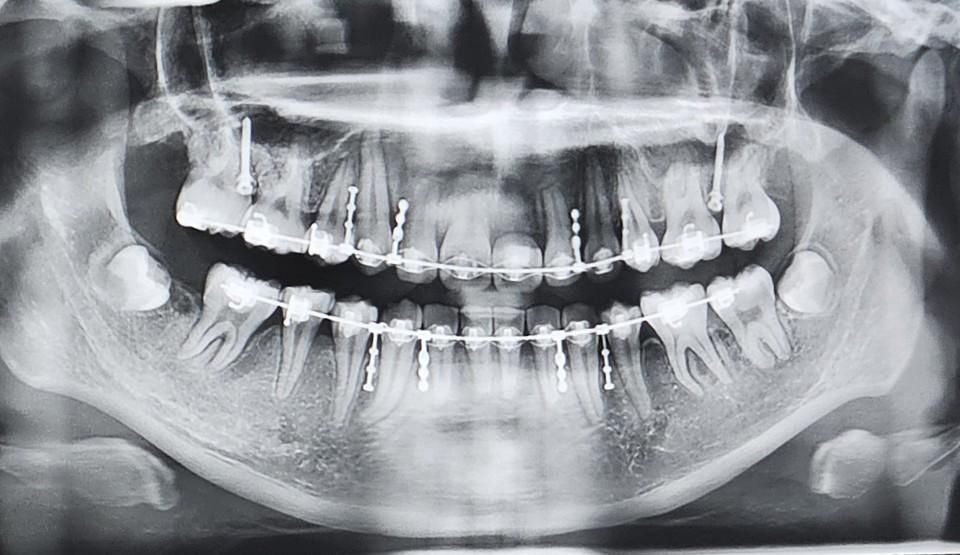

교정중 치아나 잇몸 상태 괜찮나요??

교정은 작년 4월부터 했고 이제 6개월 정도 남았다고 했습니다

발치 교정을 진행했는데 잇몸이나 치아뿌리가 짧아지는 부작용이 생긴 건 아닌지 걱정되는 마음에 질문을 올립니다! ㅠㅠ

전체적으로 치아나 잇몸에 걱정할만한 사항이 있는지 자세히 말씀해주셨음 해요! 부탁드립니다! ㅠㅠ

+앞니 하나는 임플란트 예정이라 임시치아중입니다!

해당 임시치아의 잇몸뼈도 괜찮은지 봐주시면 감사하겠습니다!

정상적인 치아 상태로 보이며, 잇몸뼈 상태로 정상적인 것으로 보입니다. 임시치아 한 부위도 뼈폭은 적당한 것으로 보이며 다만 뼈 두께는 지금 파노라마 사진상에서는 확인 안되고 ct 보아야 판별 가능합니다.

현재 사진에서 보았을 때는 뿌리 흡수 등의 부작용이 보이지 않으며 잇몸 역시 큰 문제가 없어 보입니다. 계속해서 교정을 진행하셔도 무방해보입니다. 다만 임플란트 식립 부위의 뼈를 정확히 알기 위해서는 dental-ct를 촬영해야 하며 뼈의 폭이 어느정도인지 파악을 해봐야 할 것으로 보입니다. 임플란트 식립을 위한 깊이는 괜찮아 보이나 폭이 어떨지는 ct로 판단을 해야 합니다.

전,후 사진이 둘다 있다면 좀 더 비교가 될 것 같습니다. 치아 뿌리 흡수 관련하여 뿌리의 길이의 경우 위 사진에서는 다소 왜곡되어 보이는 경우도 있습니다.